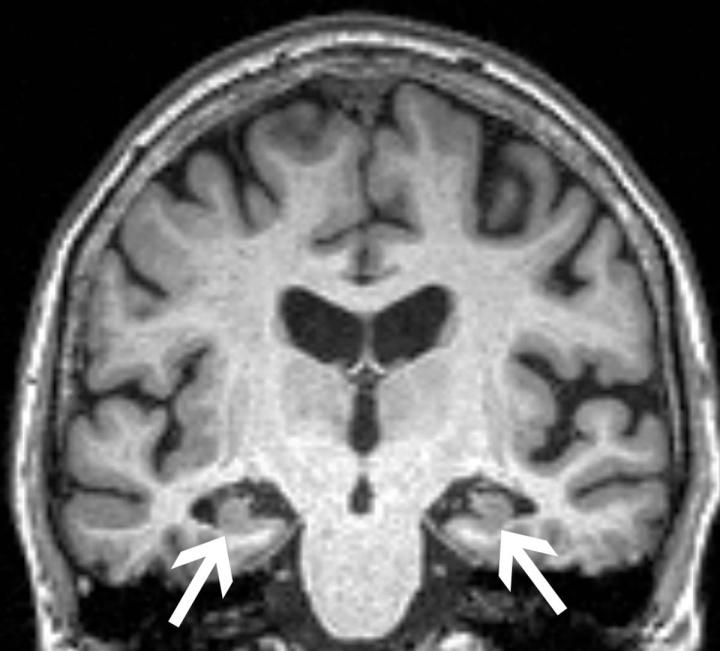

La risonanza cerebrale di una donna di 72 anni mostra la perdita di volume dell'ippocampo (frecce). La paziente aveva tutte e tre le caratteristiche (perdita del volume degli ippocampi, Apoe4 e ansia) che lo studio ha trovato associate al passaggio dal lieve decadimento cognitivo alla demenza. Fonte: RSNA

I ricercatori hanno eseguito la risonanza magnetica cerebrale per determinare i volumi di base dell'ippocampo e della corteccia entorinale, due aree importanti per la formazione dei ricordi. Hanno anche testato la presenza dell'allele ApoE4, il fattore di rischio genetico più diffuso per il MA. L'ansia è stata misurata con indagini cliniche consolidate.

Come previsto, i pazienti che sono progrediti al MA avevano volumi significativamente inferiori nell'ippocampo e nella corteccia entorinale e una maggiore frequenza dell'allele ApoE4. In particolare, però, i ricercatori hanno scoperto che l'ansia era associata in modo indipendente al declino cognitivo.